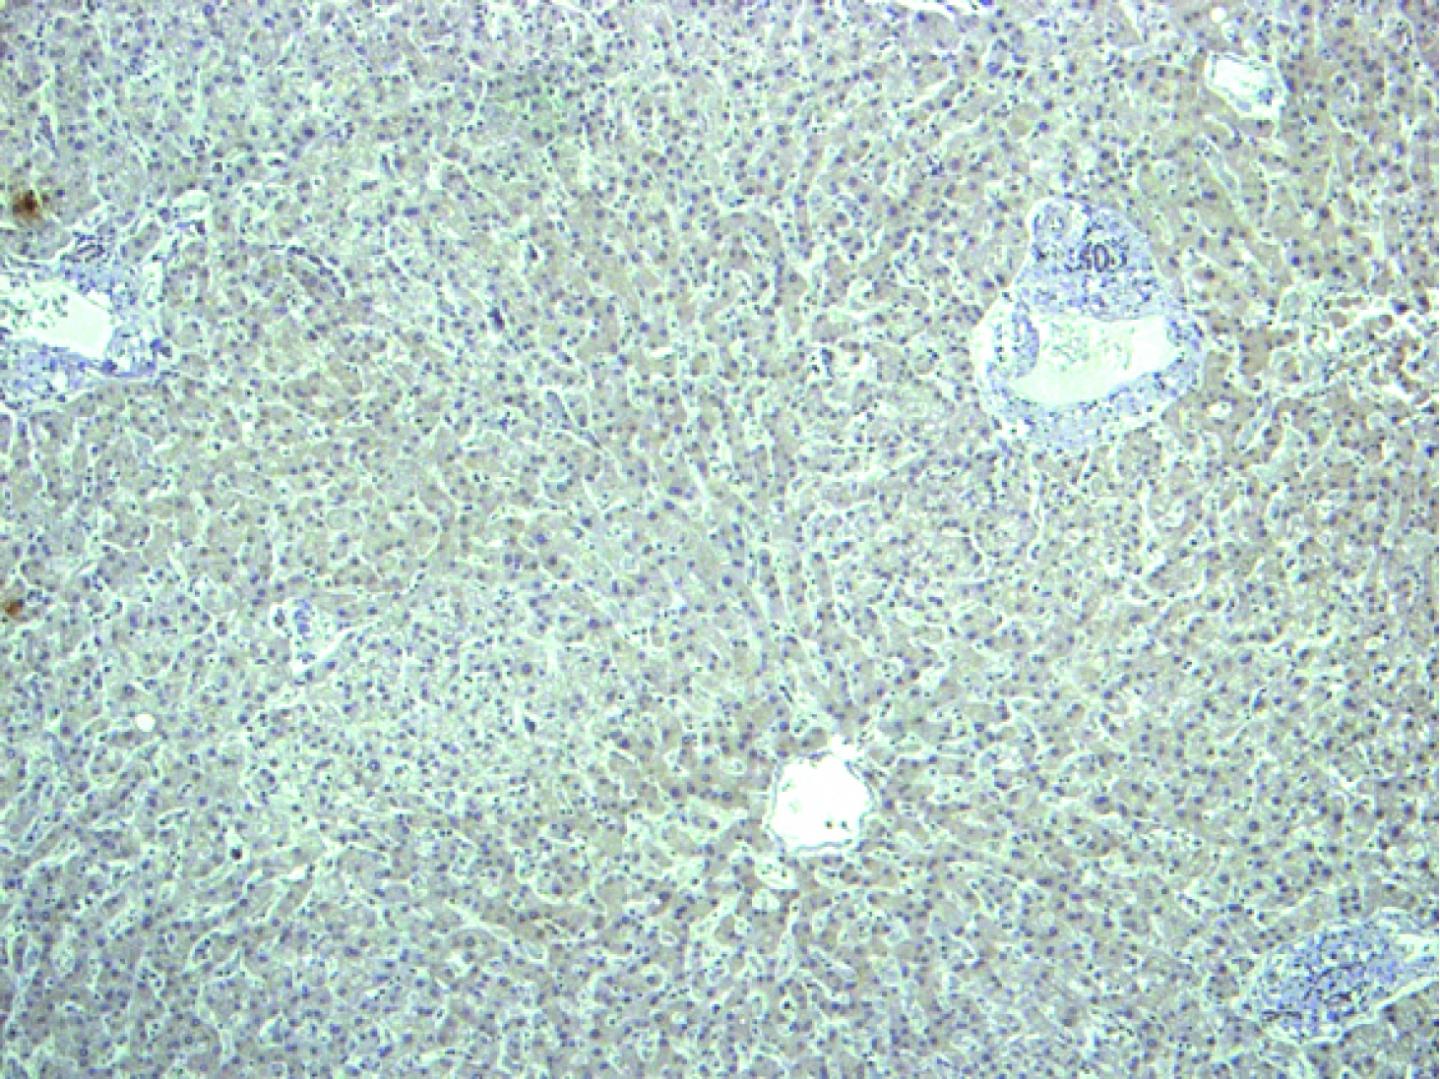

"The best about the study is that we demonstrate that the development of pathological blood vessels can be stopped by interfering with CPEB4 proteins while positive vascularisation remains intact," says Méndez. The experiments in cells in vitro, in animal models, and in samples taken from patients with cirrhosis have revealed the molecular mechanisms through which the increase in CPEB4 favours the overexpression of VEGF in cirrhosis.